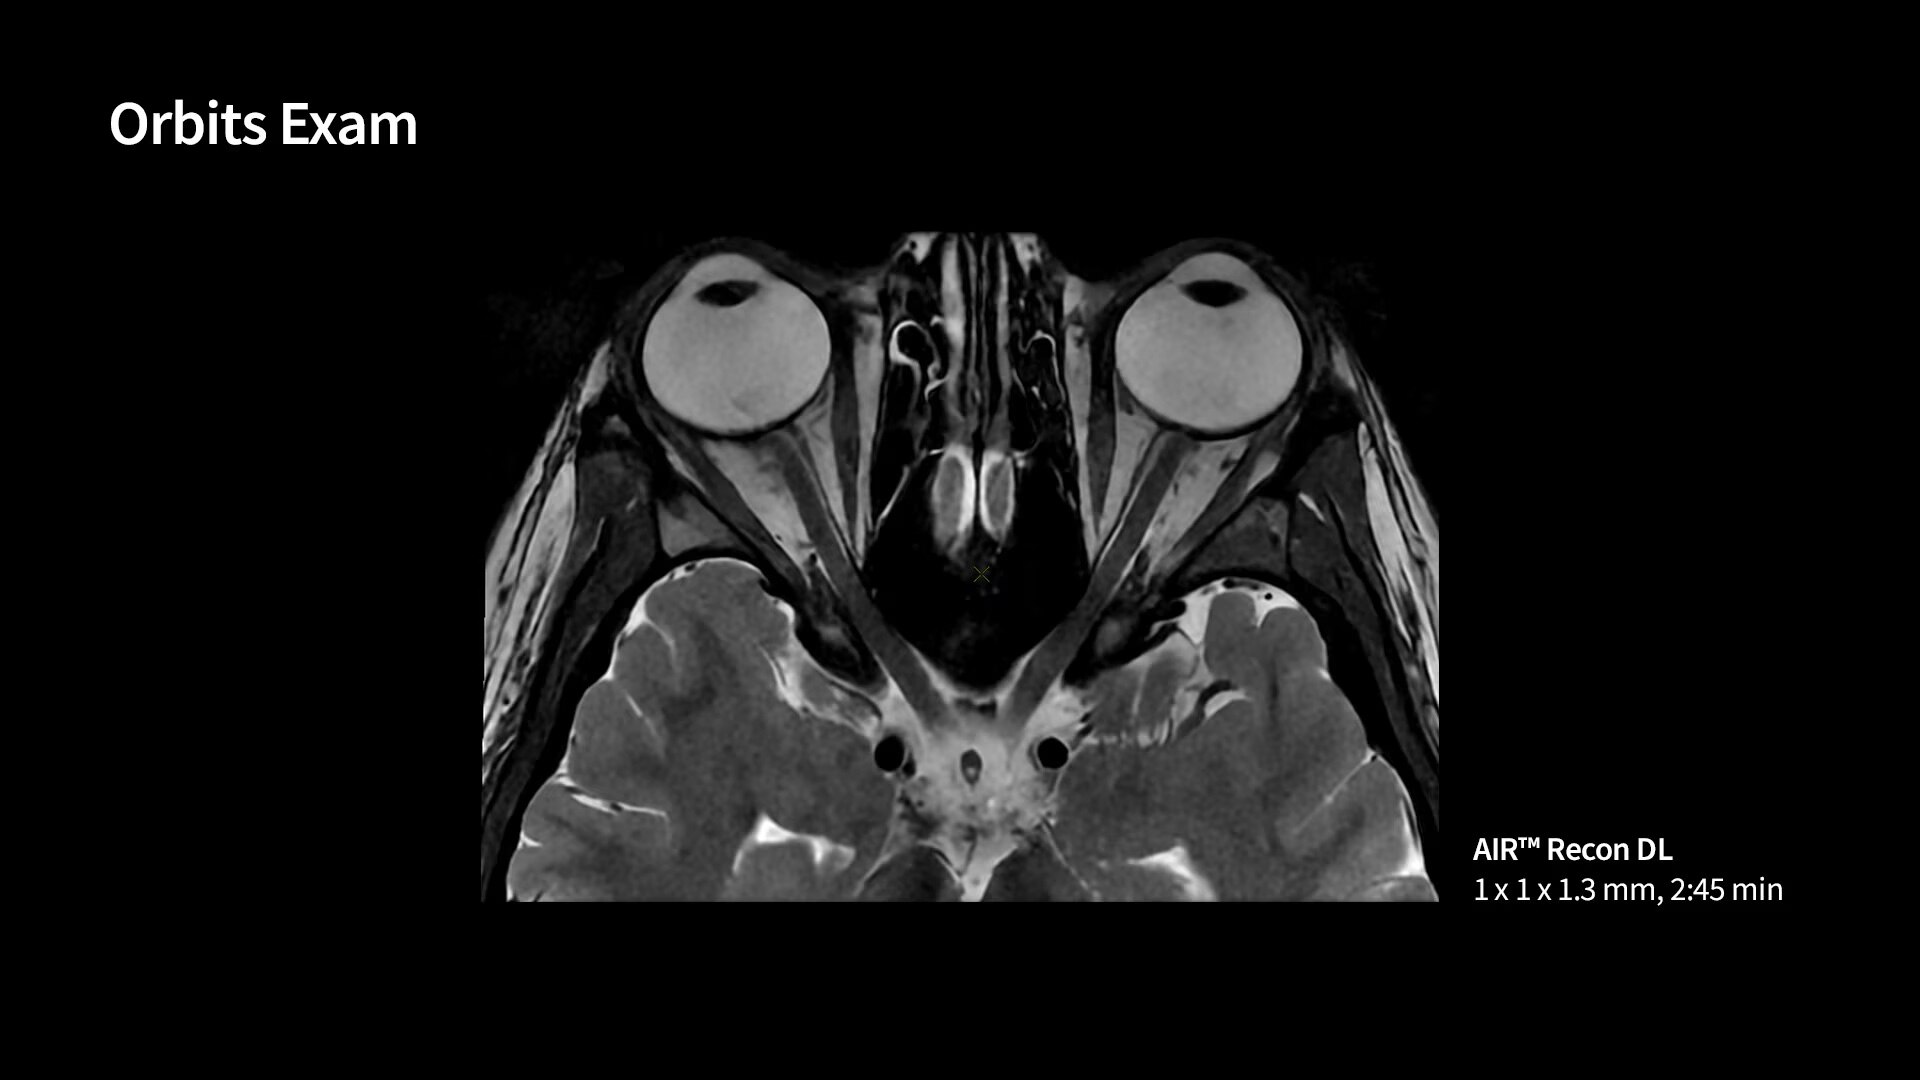

Neuro MRI for SIGNA

Explore Neuro MRI for SIGNA, a wide range of techniques for precise brain, spine and nerve anatomy to enhance treatment monitoring and neuro imaging efficiency, effortlessly.